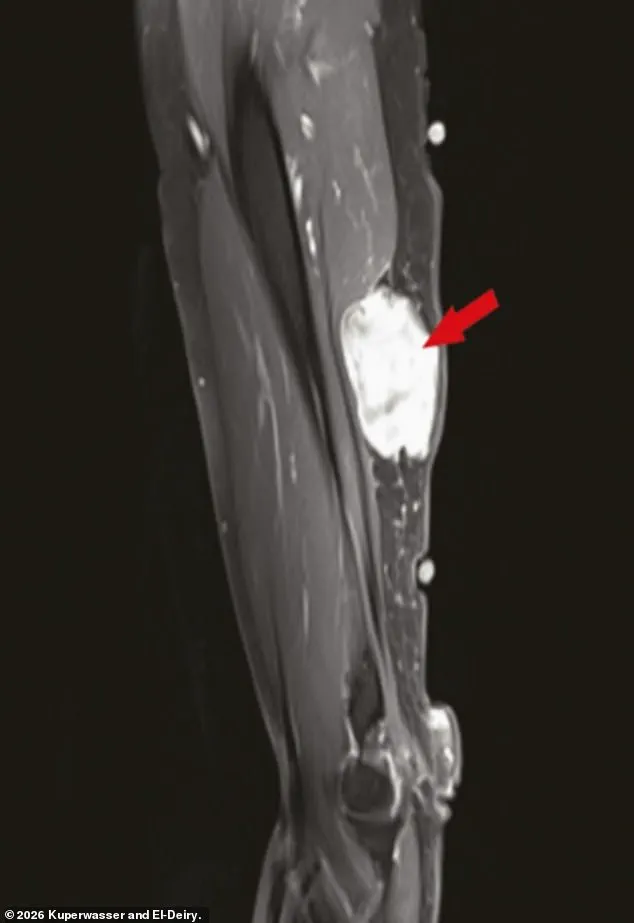

The study itself examined a range of data, including 333 cases of cancer diagnosed in the weeks and months following vaccination or booster shots.

Notably, many of the cases involved tumors growing near injection sites in the arm, a detail that has raised questions about possible localized immune responses.

However, the researchers were quick to emphasize that their findings did not establish a causal link between the vaccines and cancer.